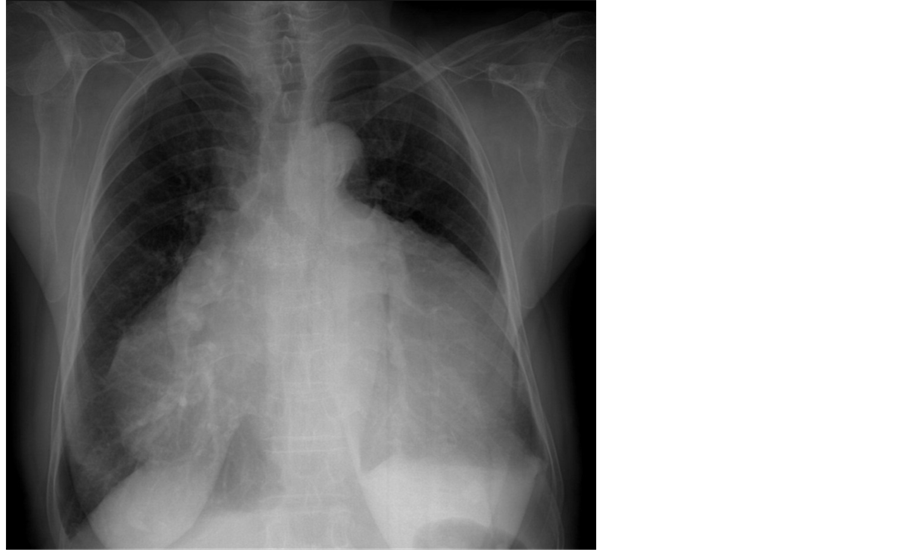

pressure 100/70 mmHg. Auscultation revealed diminished breath sounds on the right side of the chest with a dull note on percussion and a loud P2 (pulmonic component of second heart sound) with grade 2/6 soft systolic murmur over the lower left sternal border which increases in intensity with deep inspiration (Carvallo’s sign) suggesting tricuspid regurgitation. ECG revealed no arrhythmias and X-ray chest showed right- sided pleural effusion and extensive calcification over the cardiac shadow as shown in Figure 9. Transthoracic echocardiography revealed apical fibrosis of right ventricle, moderate pericardial effusion, right atrial dilatation as shown in Figure 10 and Figure 12, suggesting right ventricular endomyocardial fibrosis and severe tricuspid regurgitation as in Figure 11, Figure 13 and Figure 14 indicates coexisting pulmonary hypertension due to pulmonary damage caused by tuberculosis as shown in Figure 13 and free RV outflow tract as in Figure 15. Patient was treated with antituberculous drugs, antifailure measures such as digoxin and diuretics, ascites fluid tapping and antibiotics. He showed mild improvement in his symptoms.

A 85-year-old obese female was admitted in the cardiac intensive care unit with sudden onset of breathlessness. X-ray chest revealed massive pericardial effusion with calcification in the right ventricular region as shown in Figure 16. ECG revealed low voltage complexes. Blood chemistry revealed normal. Transthoracic echocardiography revealed large pericardial effusion with Right ventricular apical fibrosis, suggesting right ventricular endomyocardial fibrosis as shown in Figure 17 with tamponade physiology as in Figure 18 and treated with pericardiocentesis and pericardial fluid revealed an exudate on biochemical analysis.

Figure 9. X-ray chest PA (postero-anterior) view showing right-sided pleural effusion and endocardial calcification over the left ventricle in burn-out stage of EMF (endomyocardial fibrosis). ( [18] , Figure 2―left sided pleural effusion; [24] , Figure 2(a); [25] , Figure 2(c)).

Endocardial calcific deposits can be present, involving diffuse areas of the ventricles and Cockshott et al. described this feature in 1967. Calcification, an impressive finding on imaging denotes a burnt-out phase of endomyocardial fibrosis (EMF) and confirming the malignant nature of the disease. Chest X-rays show varying degrees of cardiomegaly and at times typical endocardial calcifications in the left and right ventricles as shown in Figure 9 (left ventricular endocardial calcification) ( [24] , Figure 2(a)) and in Figure 16 (right ventricular endocardial calcification) ( [25] , Figure 2(c) shows calcification in both ventricles) [26] .

A large pericardial effusion is often present and noted as another peculiar feature of this disease [27] . Pericardial effusion and ascites dominate the clinical picture of right ventricular EMF [28] [29] [30] . Etiology of pericardial effusion is possibly inflammatory and EMF is to be considered as “pancarditis” since all the layers are involved. Adhesions between the parietal and visceral layers of the pericardial sac may develop and visible as strong fibrotic strands as shown in Figure 29. A right ventricular EMF presented with massive pericardial effusion was detected in a 85-year-old female as shown in Figure 16, Figure 17 and Figure 18 [31] . Cardiomegaly can be exaggerated by pericardial effusion, and pleural effusion is also a common finding as shown in Figure 9 ( [16] , Figure 2).